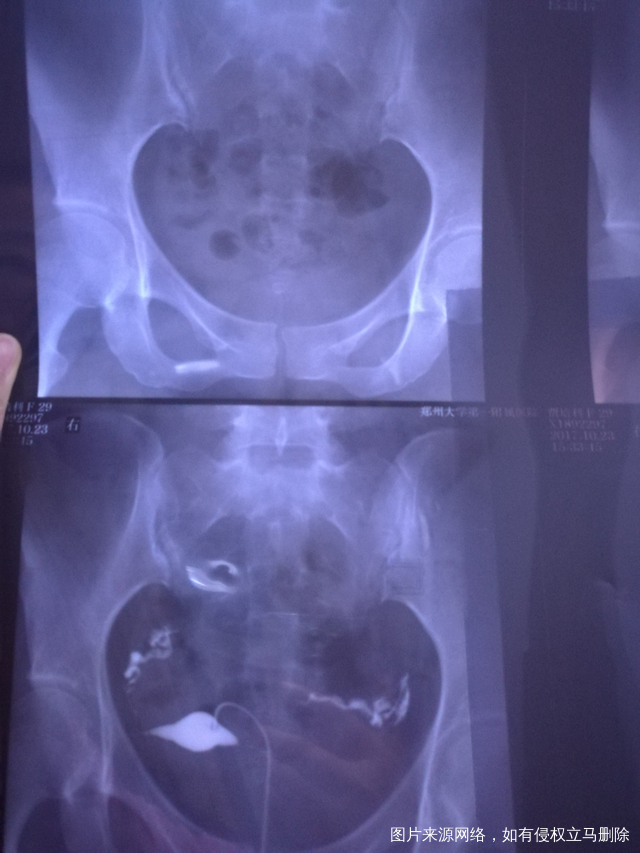

做完输卵管造影第六天了小腹还是感觉沉甸甸的如

可以热敷腹部,如果有发热,腹痛加剧,白带量多,有异味,随时就医